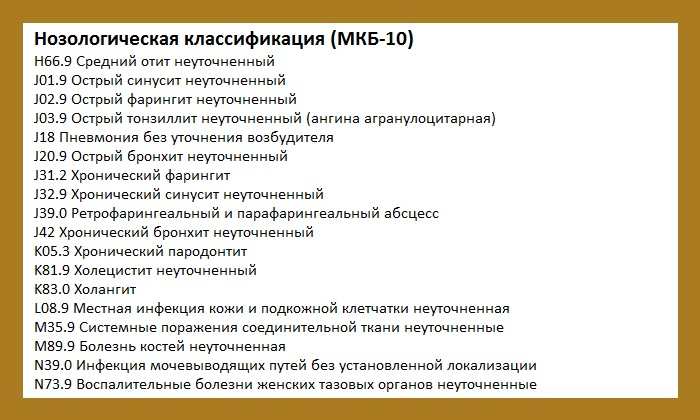

Код мкб 10 атерома головы

Код мкб 10 атерома головы 109 фото